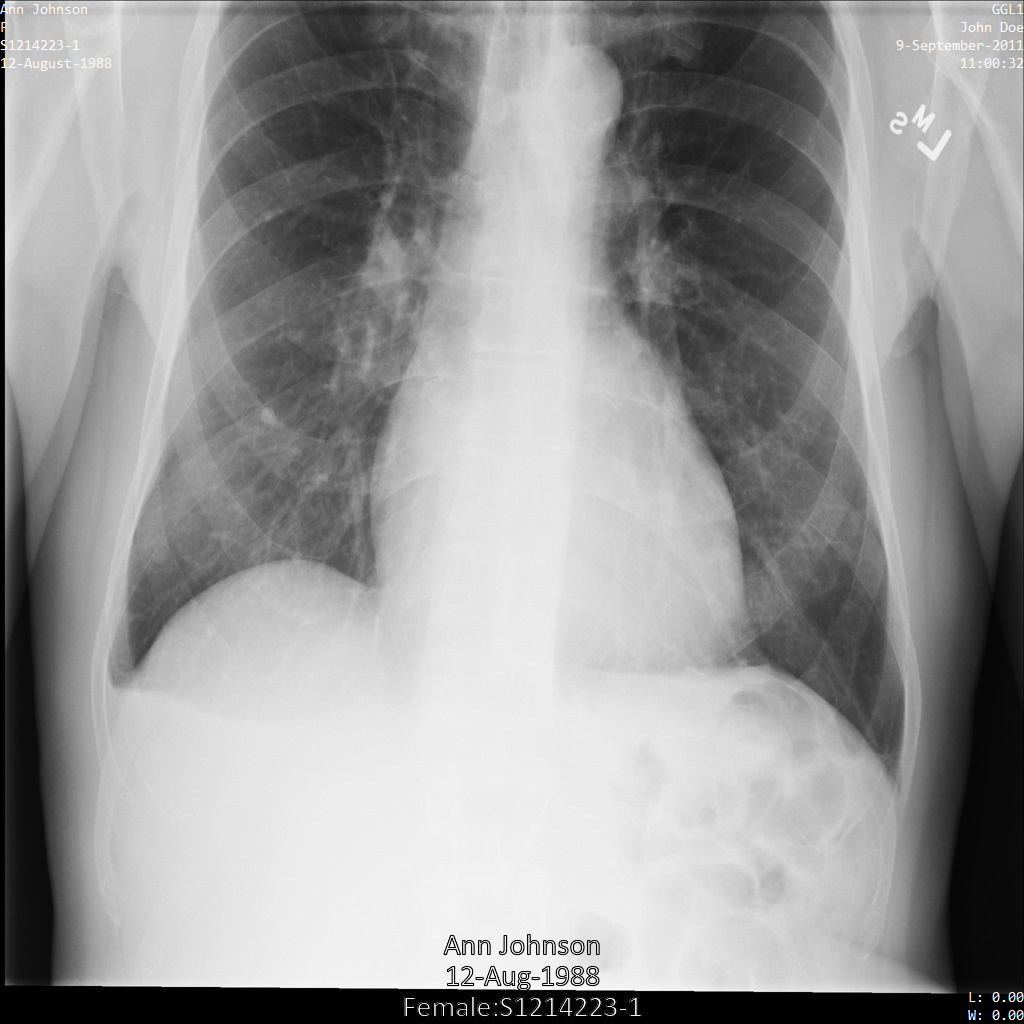

Chacune des sections suivantes fournit des exemples d'anonymisation de données DICOM à l'aide de différentes méthodes. Une sortie de l'image anonymisée est fournie avec chaque échantillon. Chaque exemple utilise l'image d'origine suivante comme entrée :

Vous pouvez comparer l'image de sortie de chaque opération d'anonymisation à cette image d'origine pour voir les effets de l'opération.

Une fois l'image envoyée à l'API Cloud Healthcare, elle apparaît comme suit. Alors que les métadonnées affichées dans les angles supérieurs de l'image ont été masquées, les informations de santé protégées qui sont incluses dans l'angle inférieur de l'image sont conservées. Pour supprimer également le texte incrusté, consultez la section Masquer le texte incrusté dans les images.